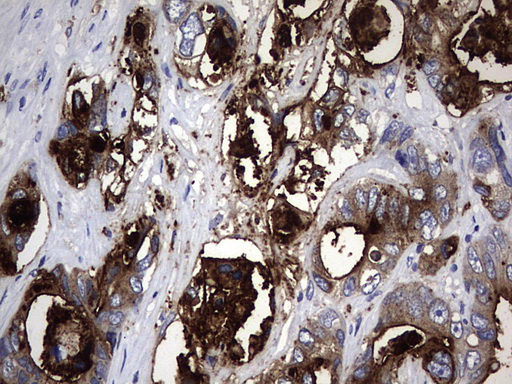

IHC analysis of CEA/CEACAM5 using anti-CEA/CEACAM5 antibody (A00356).

CEA/CEACAM5 was detected in a paraffin-embedded section of human lung cancer tissue. Biotinylated goat anti-rabbit IgG was used as secondary antibody. The tissue section was incubated with rabbit anti-CEA/CEACAM5 Antibody (A00356) at a dilution of 1:200 and developed using Strepavidin-Biotin-Complex (SABC) (Catalog # SA1022) with DAB (Catalog # AR1027) as the chromogen.